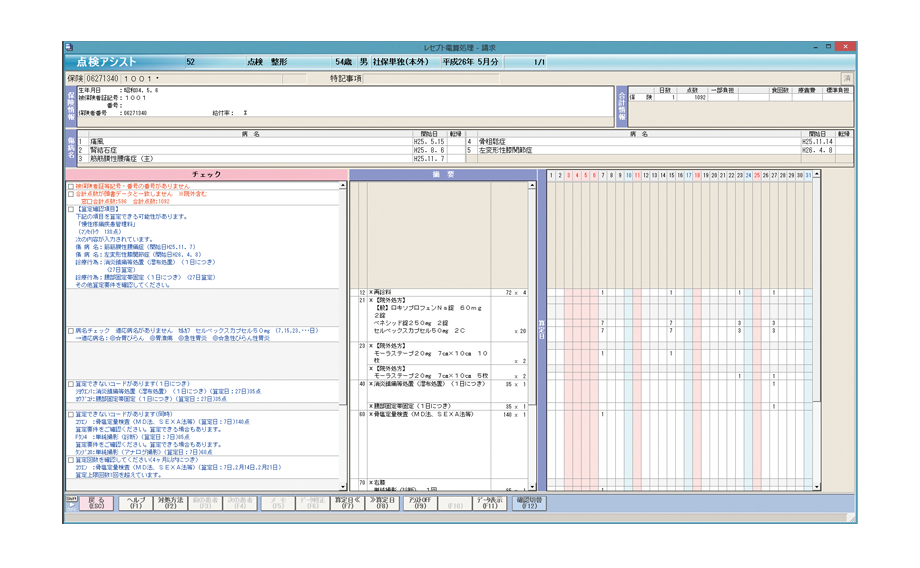

「点検アシスト」が、正確なレセプト作成をサポートします。

レセプト審査が厳格化される中、レセプト病名をチェックする機能は益々重要となっています。

さらに「突合点検」に対応するため、メディコムでは、レセプト病名の登録漏れだけでなく、投与量や投与期間、年齢などもチェックできます。